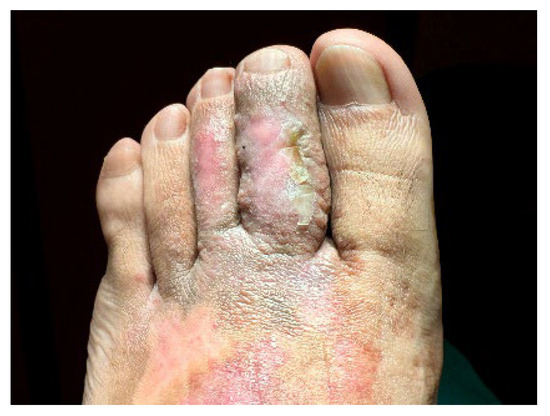

Unilateral Acroangiodermatitis: From Histopathologic Confirmation to Treatment with PDL

by André Aparício Martins, José Carlos Cardoso and André Pinho

Dermatopathology 2025, 12(4), 35; https://doi.org/10.3390/dermatopathology12040035 - 8 Oct 2025

Acroangiodermatitis is an uncommon angioproliferative dermatosis, related to chronic circulatory diseases, such as chronic venous insufficiency and arteriovenous malformations. We describe the case of a 32-year-old healthy male presenting with a pruritic, brownish lesion on the dorsal surface of the left foot, evolving [...] Read more.

Acroangiodermatitis is an uncommon angioproliferative dermatosis, related to chronic circulatory diseases, such as chronic venous insufficiency and arteriovenous malformations. We describe the case of a 32-year-old healthy male presenting with a pruritic, brownish lesion on the dorsal surface of the left foot, evolving for ten years. Physical examination revealed a brown plaque, with a verrucous surface, on the distal dorsum and medial border of the left foot. Histopathology disclosed a marked neovascularization of the upper dermis, associated with erythrocyte extravasation and hemosiderin deposition. Immunochemistry for HHV-8 was negative. CT angiography revealed multiple serpiginous vessels on the dorsum of the left foot, suggestive of a venous malformation. The diagnosis of acroangiodermatitis was established and the patient started topical corticosteroids and compression stockings, without improvement. Although scarcely described in the literature, treatment with PDL was proposed given the vascular proliferation confined to the papillary dermis. After two sessions, a significant improvement was observed. This case emphasises dermatopathology as the gold standard for the differential diagnosis with Kaposi sarcoma. In addition, it highlights PDL as a promising therapeutic option, based on the superficial histopathological location. Full article